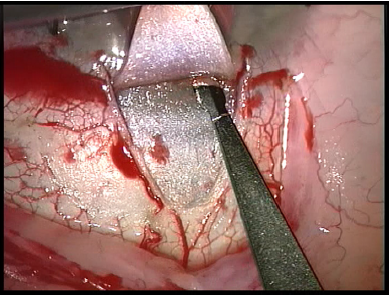

- A 4 mm by 4 mm deep scleral flap is then created within the borders of the superficial flap dissecting down to within 50 microns of the choroid. Figure 9 This dissection is carried forward into clear cornea. Schwalbe's line is carefully detached. Figure 10 The inner flap is then amputated and a large 500 micron trabeculo-descemetic window is created.